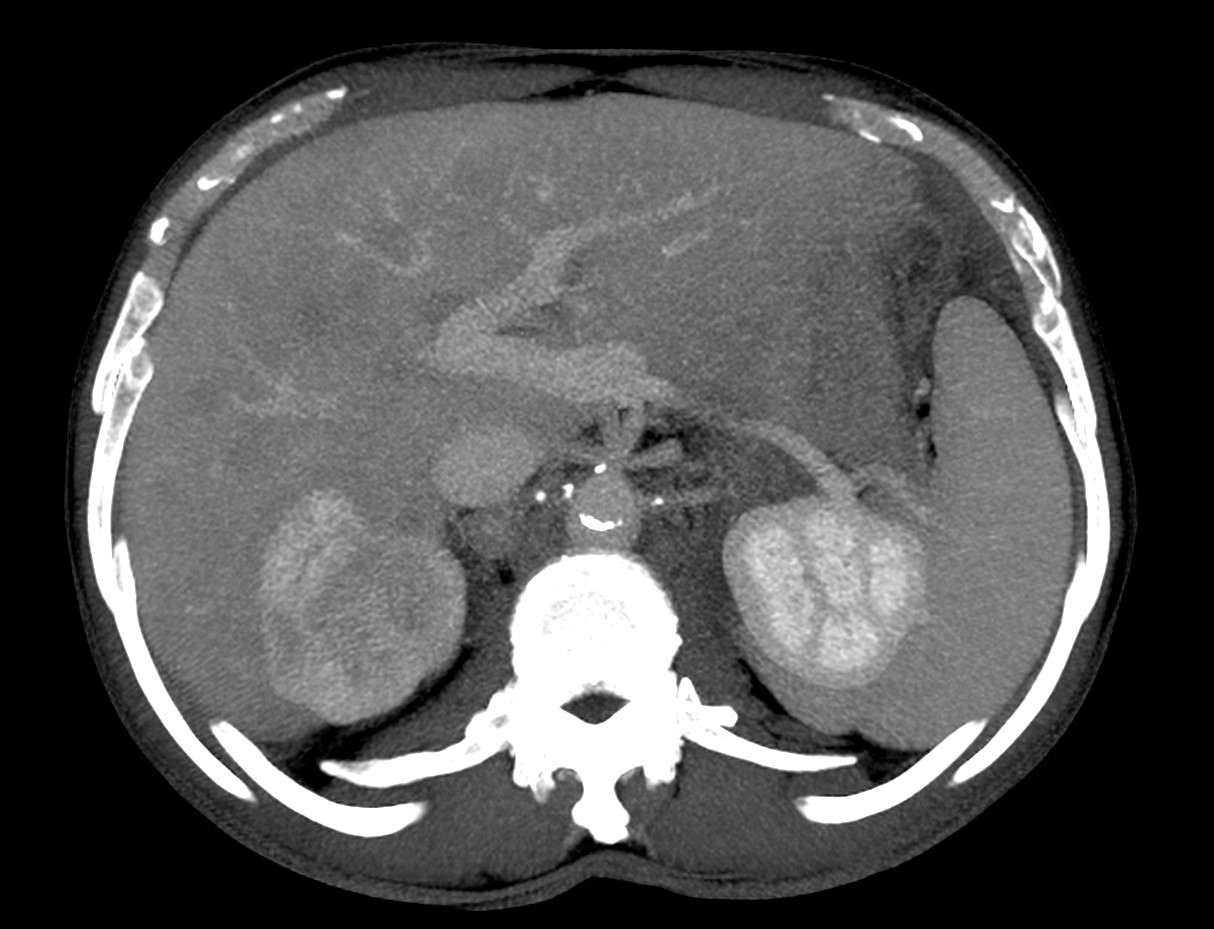

Paciente de 59 años con antecedentes personales de Cá de vejiga.

Se le realiza una Uro-Tc por seguimiento al año, aunque en esta ocasión el paciente refiere episodio de hematuria.

Tras el tratamiento de la recidiva y nefrostomía para la hidroureteronefrosis, vuelve acudir al hospital a los 9 meses por episodio de dolor en FD y malestar general. Se realiza una ecografía de urgencias.

Se realiza nueva TC bifásico abdominopélvio y Uro TC.

- Paciente con numerosas recidivas por Cá vejiga.

- Ha desarrollado un tumor metacrónico en pelvis renal derecha, también responsable de la hidroureteronefrosis.

- Mala evolución radiológica del proceso a expensas de metástasis pulmonares y hepáticas.